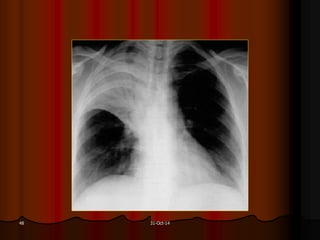

31-Oct-1448

31-Oct-1449